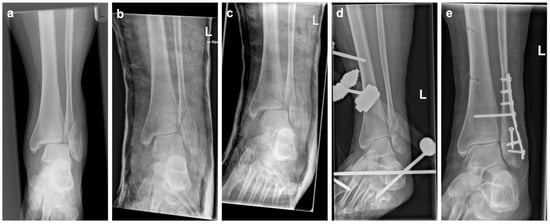

Figure 1. Example of a unimalleolar ankle fracture dislocation, with radiographs taken prereduction (a), postreduction with improved joint position in the cast (b), and after loss of reduction in the cast 3 days later (c). Subsequently, ExFix was applied (d) before definitive ORIF was performed (e).

In the second group, a plaster cast was applied for immediate fracture immobilization after fluoroscopically controlled closed reduction in the emergency department. As soon as the plaster cast had dried, radiographic imaging was performed to assess adequate reduction, with a medial clear space of <5 mm and uniform width of the tibiotalar and tibiofibular joint space (Figure 1) [6]. Directly afterwards, medial and lateral cuts were applied to the cast, in accordance with AO/OTA principles. After applying the cuts, the cast was held in place by elastic bandages to allow for posttraumatic soft-tissue swelling. All patients were admitted as inpatients for elevation and soft-tissue control.

In case of (persistent) dislocation in postreduction radiographs, these events were not considered secondary LOR because there was no radiographic proof that, after cast application, adequate reduction of the ankle joint had been restored. In all these cases, immediate treatment with ExFix was performed. Consequently, these patients were included in the ExFix group.